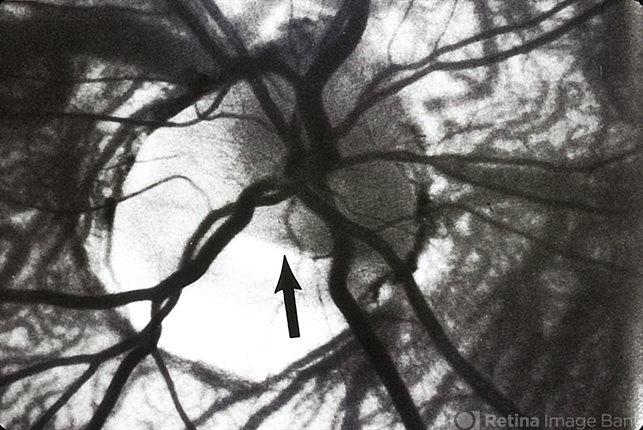

- optic nerve pit, red-free

- Optic Nerve Head Pit Red Free Photo